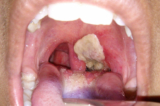

Bệnh bạch hầu đặc trưng bởi lớp giả mạc tuyến hạnh nhân, thanh quản, hầu họng, mũi, có thể xuất hiện ở da, kết mạc mắt hoặc bộ phận sinh dục.

- Bạch hầu họng, mũi: Bạch hầu họng, mũi đặc trưng bởi lớp giả mạc dày và dai, màu trắng ngà, bám chắc vào amidan hoặc có thể lan rộng bao phủ cả vùng vòm họng. Bệnh nhân có thể có triệu chứng sưng to các hạch vùng cổ và vùng dưới hàm.

Khi vi khuẩn bạch hầu phát triển trong lớp lót ẩm bên trong mũi và cổ họng sẽ bắt đầu tạo ra một lượng lớn chất độc. Chất độc này giết chết các tế bào và tạo ra một lớp màu trắng đục gọi là giả mạc. Giả mạc được hình thành từ tế bào chết, vi khuẩn, chất thải và protein.

Giả mạc này có thể bao phủ các mô mũi, amidan, thanh quản và phần còn lại của cổ họng. Đây là triệu chứng rõ ràng nhất của bệnh bạch hầu và có thể khiến bệnh nhân khó thở và khó nuốt.